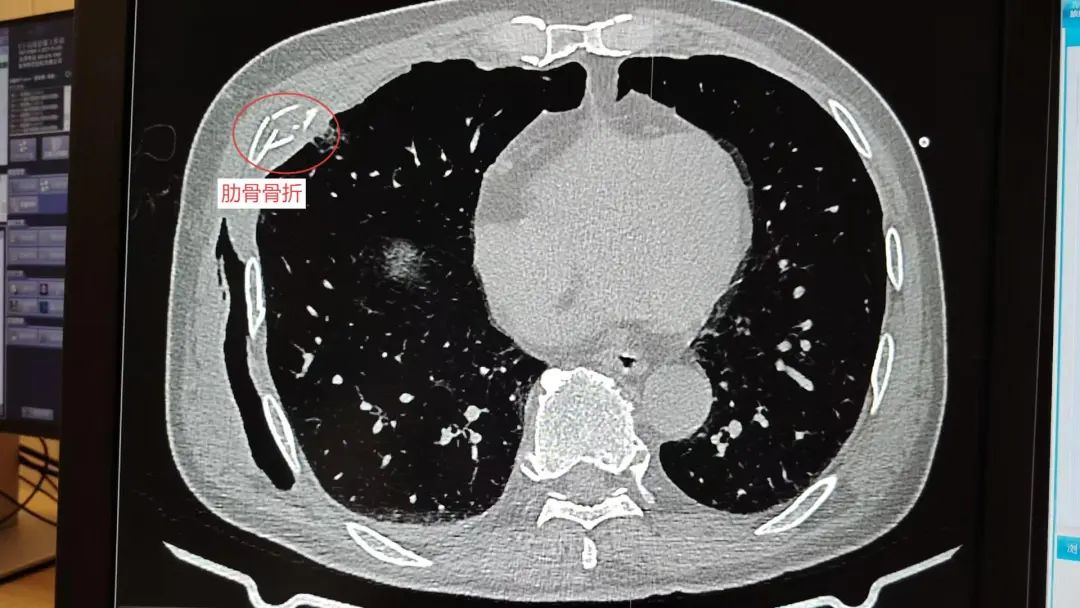

多处骨折

系统检查提示:罗叔目前存在车祸后多发伤,头部、胸部、腹部等存在多处外伤,颅脑的挫裂伤,右侧颌面部撕裂伤,右肘关节皮肤裂伤等全身多处皮肤擦伤。外表的伤口已经足够狰狞,而在罗叔的身体内部存在更严重的情况:闭合性颅脑损伤、呼吸衰竭、右侧6根肋骨骨折伴血气胸和皮下气肿、代谢性酸中毒、呼吸性碱中毒,还有肝、肺挫伤等脏器损伤。